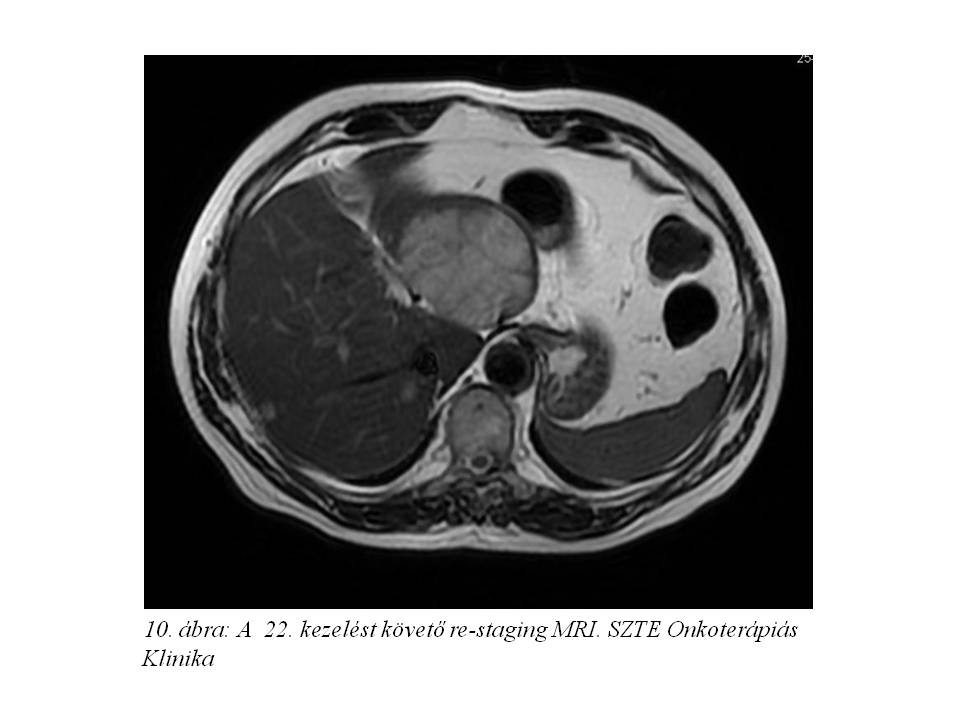

Octreotid monoterápiáját (Sandostatin LAR kezelés) 2012.04.27-én kezdtük, az első injekció beadását követően arcpirosodása és hasmenése megszűnt. A 4. kezelést követően re-staging MR vizsgálaton (8. ábra) minimális regressziót véleményeztek (2012.08.10.), chromogranin 128 ng/ml-re csökkent. A 8. kezelést követően képalkotóval továbbra is stabil betegség állt fenn, azonban a chromogranin érték emelkedni kezdett (185,4 – 197,30 – 200,5 – 266,0 – 283,9 ng/ml). A definitív progresszió hiánya (7%-os növekedés, SD) miatt kezelését folytattuk, összesen 22 ciklust kapott 2013.12.02-ig (9. ábra, 10. ábra).

Ezt követően bőrgyógyászati ellátás vált szükségessé testszerte jelentkező viszkető urticaria miatt, felmerült octreotidra való túlérzékenység lehetősége. Emiatt kezelését a továbbiakban lanreotiddal (Somatuline) folytattuk, ugyancsak 4 ciklusonként végzett re-staging mellett. Jelenleg a hasi MR vizsgálaton (11. ábra, 12. ábra, 13. ábra) változatlan status látható, a chromogranin szint emelkedése mellett (266,9 – 310 – 427 ng/ml).